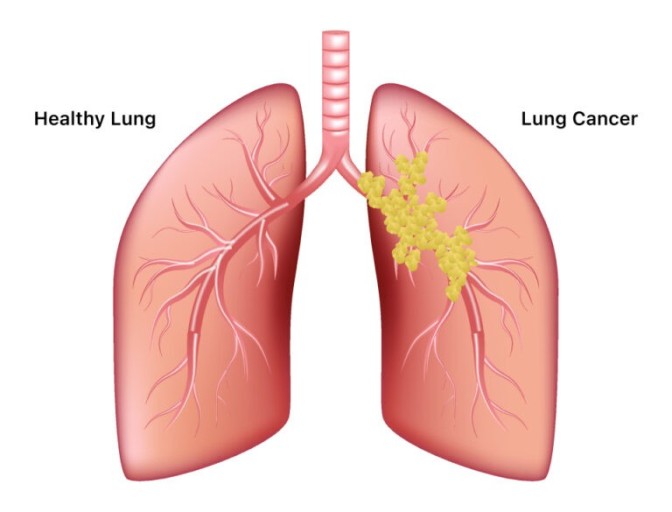

폐암은 위암, 갑상선암 다음으로 3번째로 발병 빈도가 높은 3대 암 중 한 가지인데요. 폐암은 재발과 전이까지의 빈도도 잦은지라 완치가 어렵다고 하며 폐암 발병 초기에는 거의 증상이 없을 수가 있어 수술이 불가능한 3기, 혹은 4기에 주로 진단된다고 해요.

폐암 초기증상 폐암 4기에 이르게 되면 5년 생존률이 30% 대로 감소하게 된다고 해요. 그리하여 폐암은 암 질병이자 중 사망자 비율이 가장 높은 것으로 나타나고 있어요.

폐암은 사망률 2위를 차지하고 있는 간암에 비해 무려 2배에 가까운 사망률을 보이고 있다고 합니다. 이렇게 치명적인 폐암에 대해 미리 알고 대처하는 것이 바람직할 것 같아요. 아래에서는 폐암이라 판단해 볼 수 있는 그 초기증상에 대해 간단히 설명드릴게요.